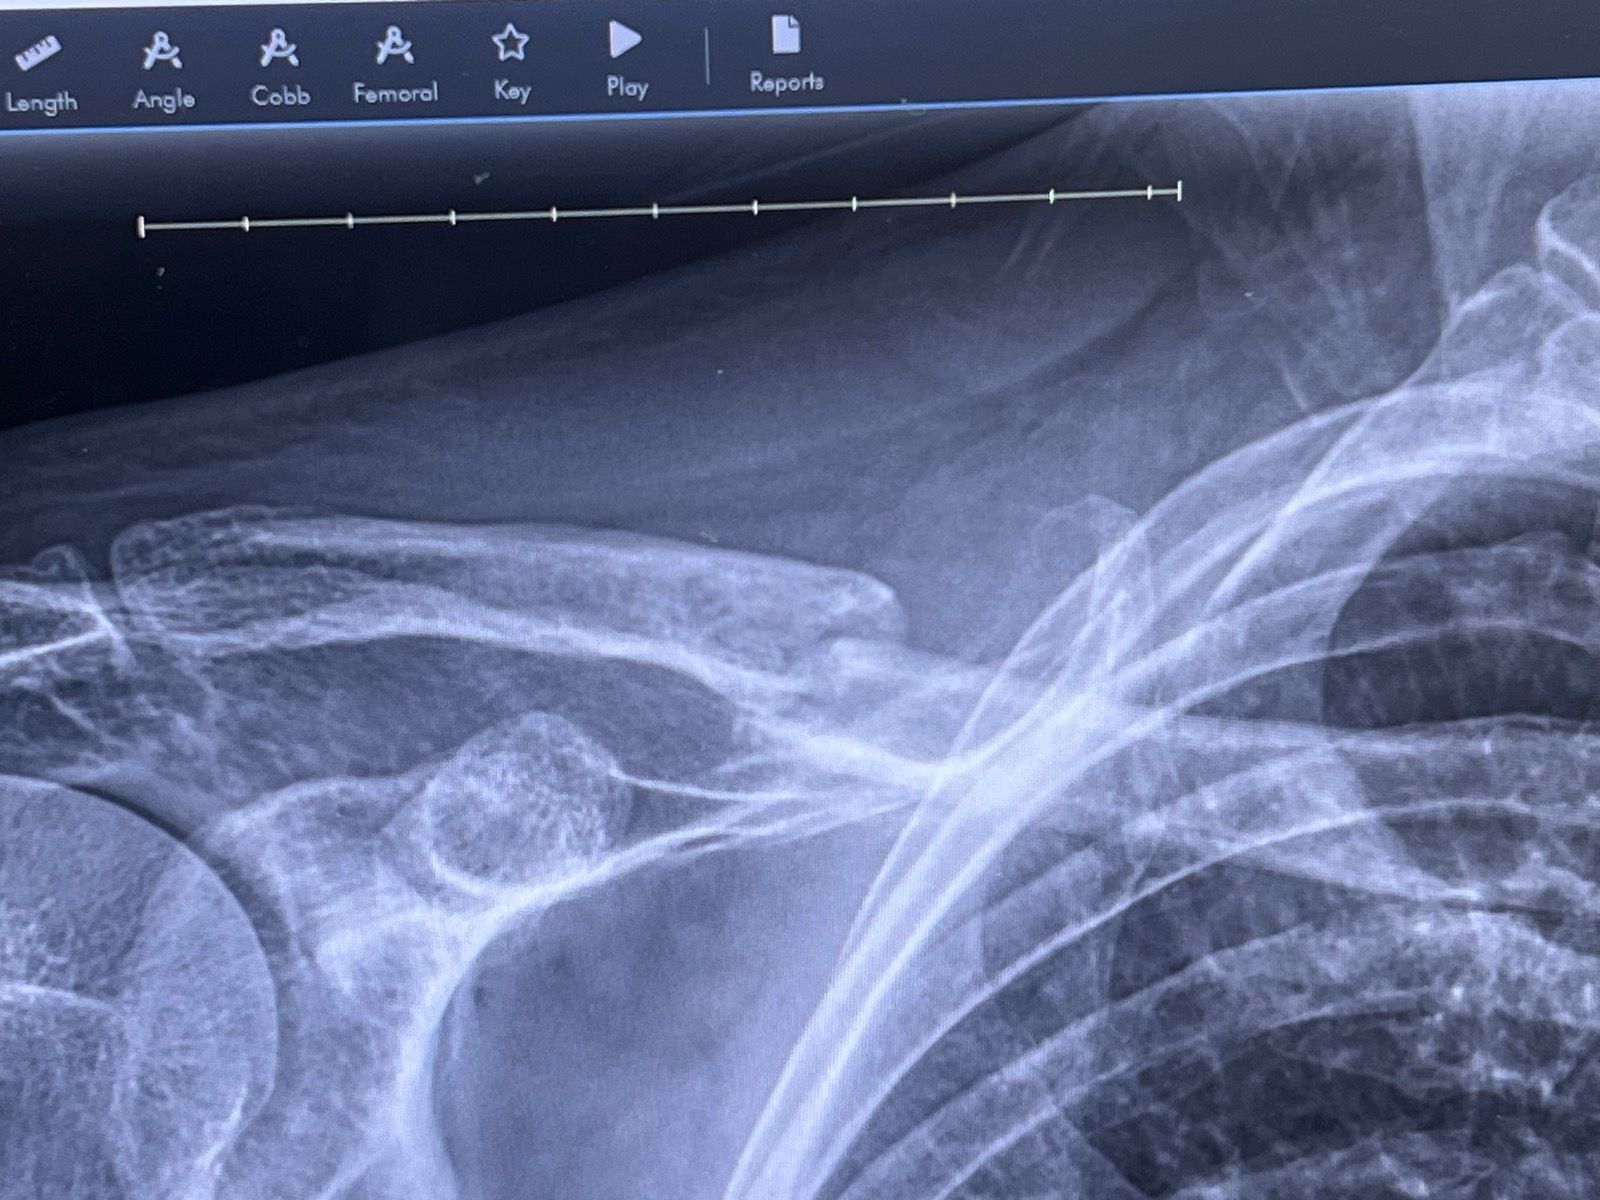

Hey everyone I’m 26 years old about two weeks ago I experienced a little accident and broke my clavicle ( collar bone) currently I don’t have much pain at all. I spoke with couple of orthopaedic doctors and they said I am able to heal cosmetically but there is always the option of doing the surgery. I would just like to hear your opinions and feel free to leave some advice for fast healing. I placed a picture of my x-ray for y’all to see the damage and perhaps you may have experienced or know someone that experienced a similar break. Feel free to leave your advice based on my picture. Thank you for your time

Yours is a clean break but there is a some seperation. How will those two pieces line back up? Will wearing a brace re-align them so they can grow back together? If it was me and I had the choice, I would get the plate. It is an easy surgery and you will recover from it much faster. I was back on my bike outside in three weeks after my first break and it was broken in 3 places. On the second break I was back outside after a week, but my doctor said it was the easiest clavicle surgery he ever did since the plate kept everything together. He Just had to remove the bent twisted plate and place in a new one and staple me back up.